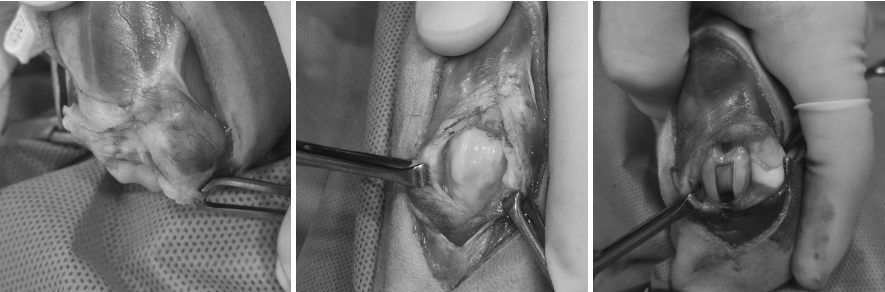

환자에게 시행된 수술은 단순 정복이 아닌, 슬개골 탈구의 구조적 원인을 교정하는 수술이었습니다.

1️⃣ 활차구 성형술

얕아진 대퇴골 고랑을 깊게 만들어 슬개골이 다시 빠지지 않도록 안정성을 확보했습니다.

2️⃣ 경골조면이식술

정강이뼈의 정렬을 바로잡아

슬개골에 가해지는 비정상적인 힘을 교정했습니다.

수술 전 무릎고랑 사진(좌, 중) / 수술 후 깊어진 무릎고랑 사진(우) / 출처: 미래동물의료센터